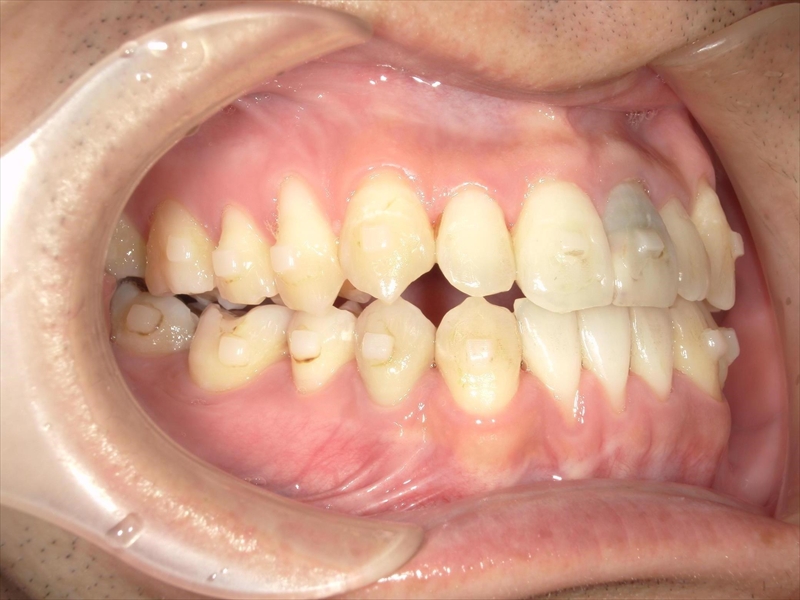

下の歯は、受け口気味で、さらに右下の前から2番目の歯が1本足りない状態でした。

また、歯並び全体がお顔の中心よりも右にずれており、噛み合わせも左右で違っていました。

右側では下の歯が前に出すぎており、左側では逆に下の歯が少し後ろに下がっているという、左右でバランスの取れていない噛み合わせでした。

このような状態を改善するため、歯を同じ方向に動かすのではなく、左上の奥歯は後ろへ、右下の奥歯も後ろへと、斜め方向に歯を動かす治療計画を立てました。

これにより、歯並びのズレや噛み合わせの左右差を少しずつ整えていきました。

治療前後 写真